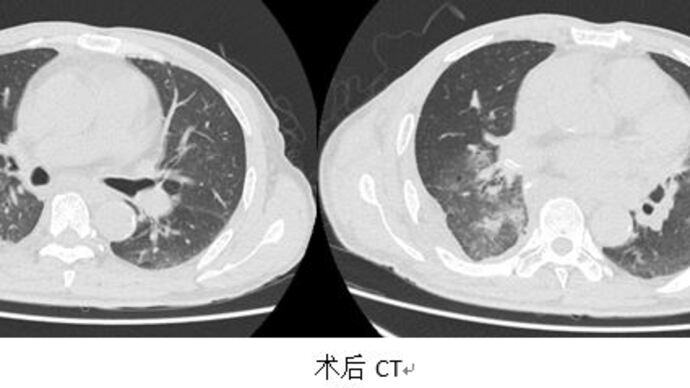

8年前罕见患乳腺癌63岁上海爷叔胸腔又长占据75的巨大肿瘤